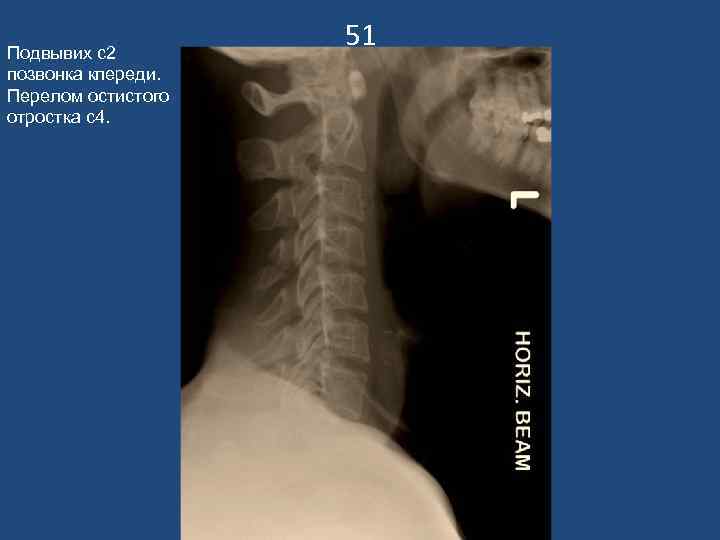

Подвывих с2 позвонка кпереди. Перелом остистого отростка с4. 51